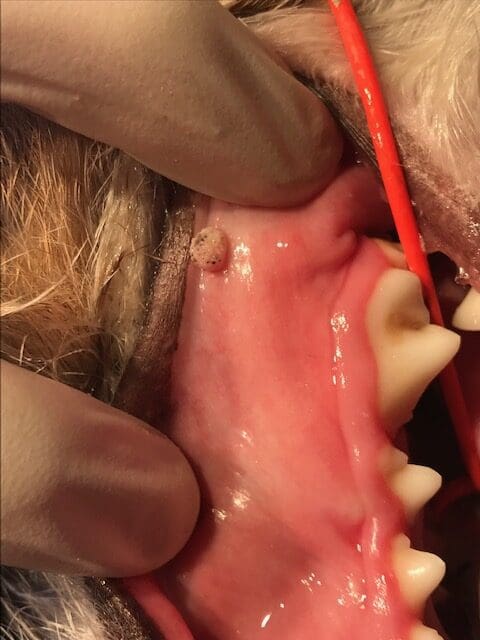

Papillomas most commonly occur on the face, lips, extremities, and within the oral cavity. These warts are generally small in appearance and pale to pink in color. They tend to be cauliflower-like and may enlarge and become darker over time. Papillomas are typically asymptomatic, producing or showing no symptoms, but may cause oral discomfort and interfere with breathing if large in size or numerous in quantity. A confirmed diagnosis is completed by biopsy and histopathology.